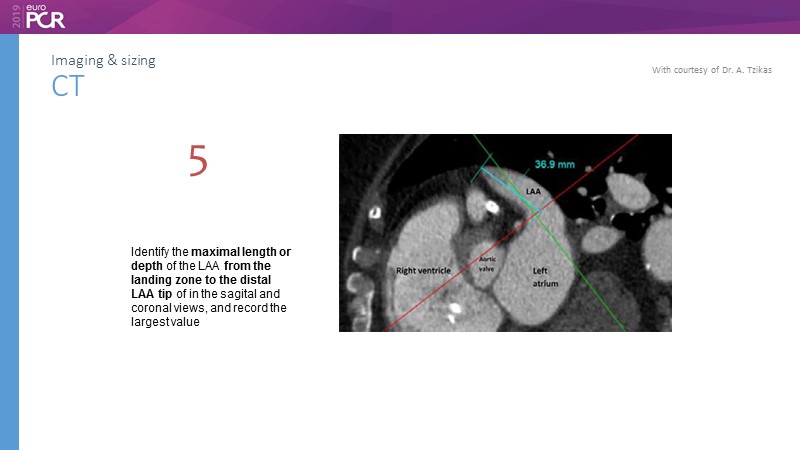

Pre-procedure planning

Previous Next